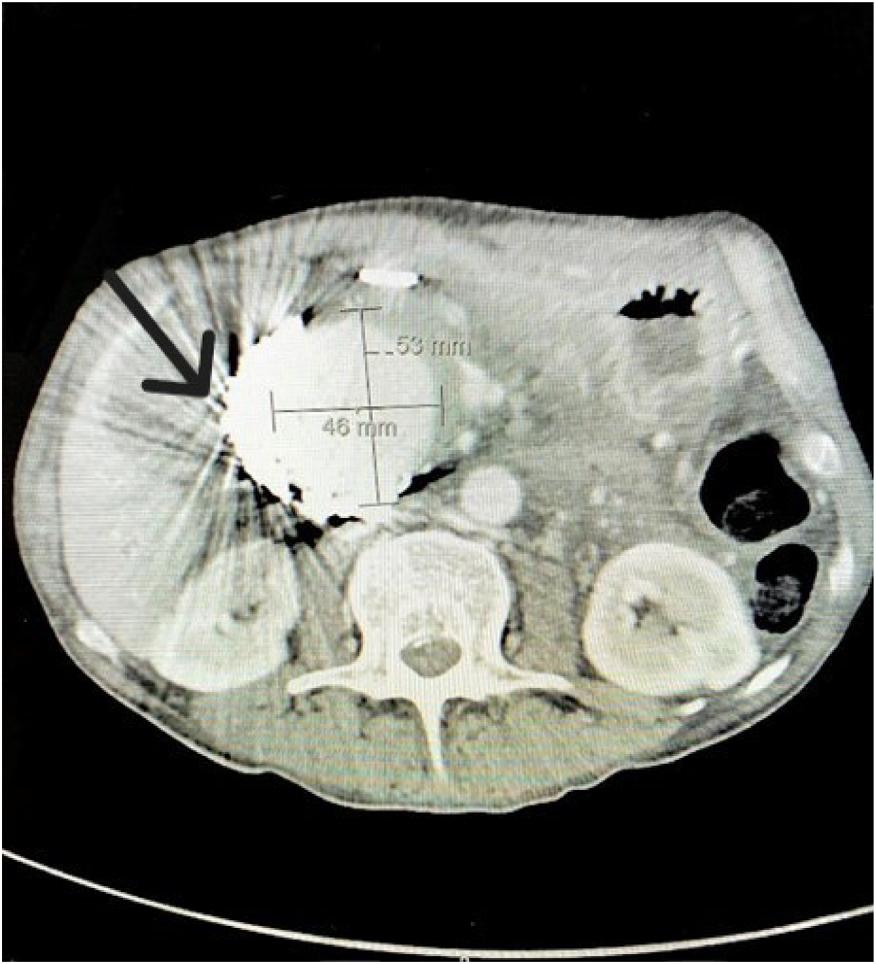

Achestradiograph(CXR)(Image1)showedalargehiatal herniawithtracebilateralpleuraleffusionsanddisplacement ofthegastricbubbletotheright.Computedtomography (CT)withcontrastofthechest/abdomen/pelvis(Images2 and 3)demonstratedalargehiatalherniawithmostofthe stomachinthechest,associatedvolvulus,bilateralpleural effusions,rightgreaterthanleft,andacomplex,partially fluid-filledcollectionalongtheposterioraspectofthehiatal

Anterior-posteriorchestradiographdemonstratinglarge hiatalherniawithdisplacementofthegastricbubble(arrow)from lefttoright.

Image3. Transverseviewofcomputedtomographyofthechest/ abdomen/pelviswithanarrowindicatingpartially fluid-filled collectionposteriortoalargehiatalherniasuspiciousfor esophagealperforation.

Image1. Image2. Coronalviewofcomputedtomographyofthechest/ abdomen/pelvisshowinglargehiatalhernia(arrow).Thepatientunderwentanexploratorylaparotomy,which confirmedthepresenceofanesophagealrupturenearthe squamocolumnarjunctionandrevealedthepresenceofa gianthiatalherniawithanassociatedupside-downstomach. Surgicalrepairoftheesophagealperforationandgastropexy wasperformed.Thepatientwasadmittedtothesurgical intensivecareunitforatotalof fivedaysduringwhich shehadanepisodeofatrial fibrillationwithrapidventricular responsethatresolvedaftermetoprololanddiltiazem.